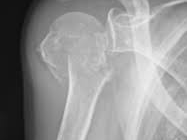

어깨에 골절이 발생하면 일상 전체가 마비되는 기분을 느끼는 것도 무리는 아닙니다. 특히 쇄골, 상완골 근위부, 견갑골 부위에 골절이 생기면 수술이 필요하며, 수술 이후의 재활과 물리치료는 단순히 통증을 없애는 것을 넘어, 관절 가동 범위의 회복과 장기적인 기능 정상화를 위한 핵심 단계입니다. 또한 어깨 골절 수술 이후 본격적으로 시작되는 재활 치료와 도수치료의 현실적인 문제는 ‘비용’과 ‘보험 적용 여부’입니다.